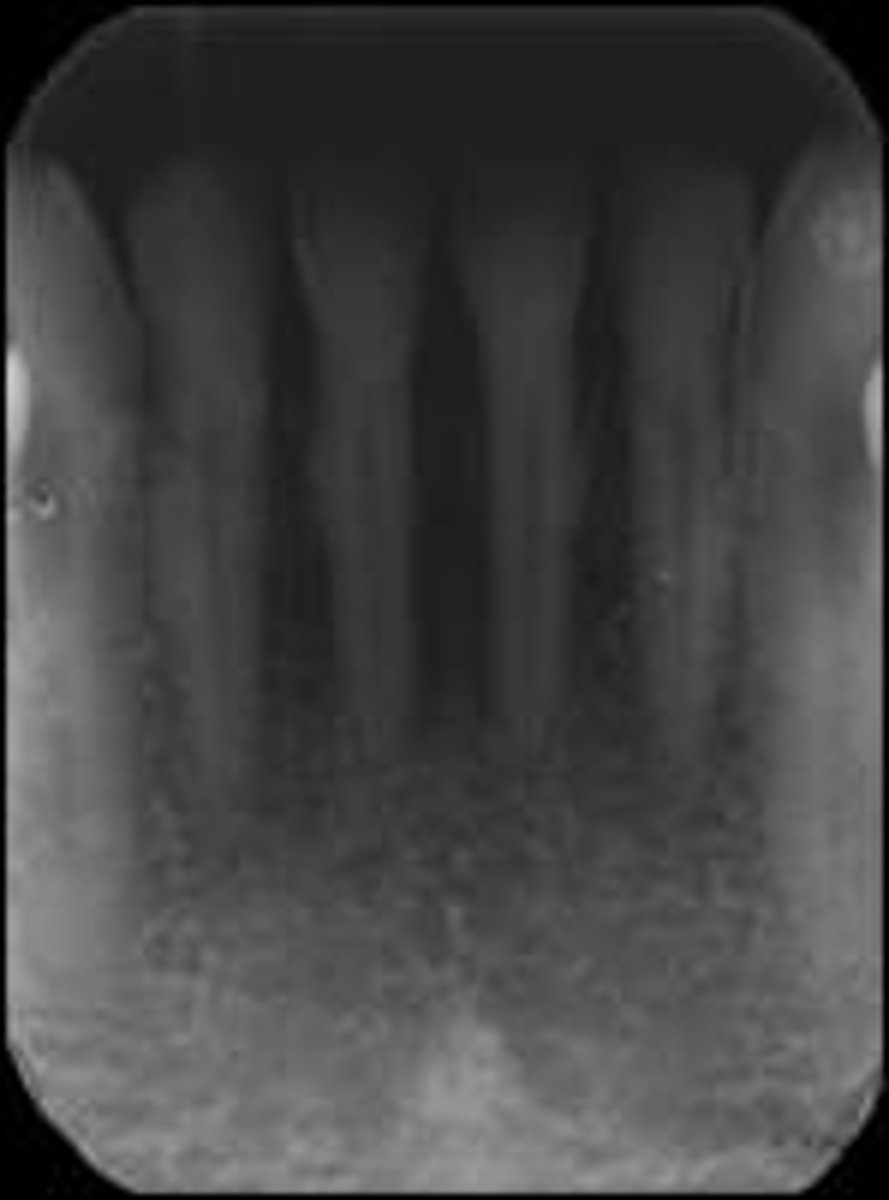

Underexposed film